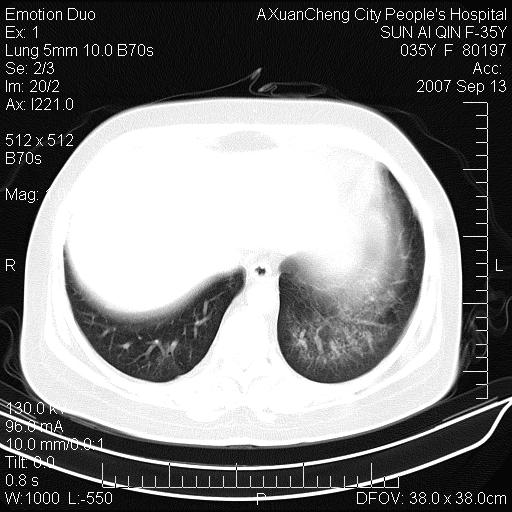

以下是引用天南地北在2007-9-13 13:43:00的发言:[br]考虑双肺、肺门侵润

以下是引用ydx_74在2007-9-13 15:42:00的发言:[br]仅看片,考虑右上肺癌并双肺转移,结合病史,考虑肺门、肺内淋巴侵润

以下是引用同在2007-9-13 15:08:00的发言:[br]支持肺门及双肺侵润.